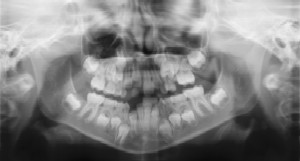

Dental Radiographs (X-Rays)

Radiographs (X-Rays) are a vital and necessary part of your child’s dental diagnostic process. Without them, certain dental conditions can and will be missed.

Radiographs detect much more than cavities. For example, radiographs may be needed to survey erupting teeth, diagnose bone diseases, evaluate the results of an injury, or plan orthodontic treatment. Radiographs allow dentists to diagnose and treat health conditions that cannot be detected during a clinical examination. If dental problems are found and treated early, dental care is more comfortable for your child and more affordable for you.

The American Academy of Pediatric Dentistry recommends radiographs and examinations every six months for children with a high risk of tooth decay.

Pediatric dentists are particularly careful to minimize the exposure of their patients to radiation. With contemporary safeguards, the amount of radiation received in a dental X-ray examination is extremely small. The risk is negligible. In fact, the dental radiographs represent a far smaller risk than an undetected and untreated dental problem. Lead body aprons and shields will protect your child. Today’s equipment filters out unnecessary x-rays and restricts the x-ray beam to the area of interest. High-speed film and proper shielding assure that your child receives a minimal amount of radiation exposure.